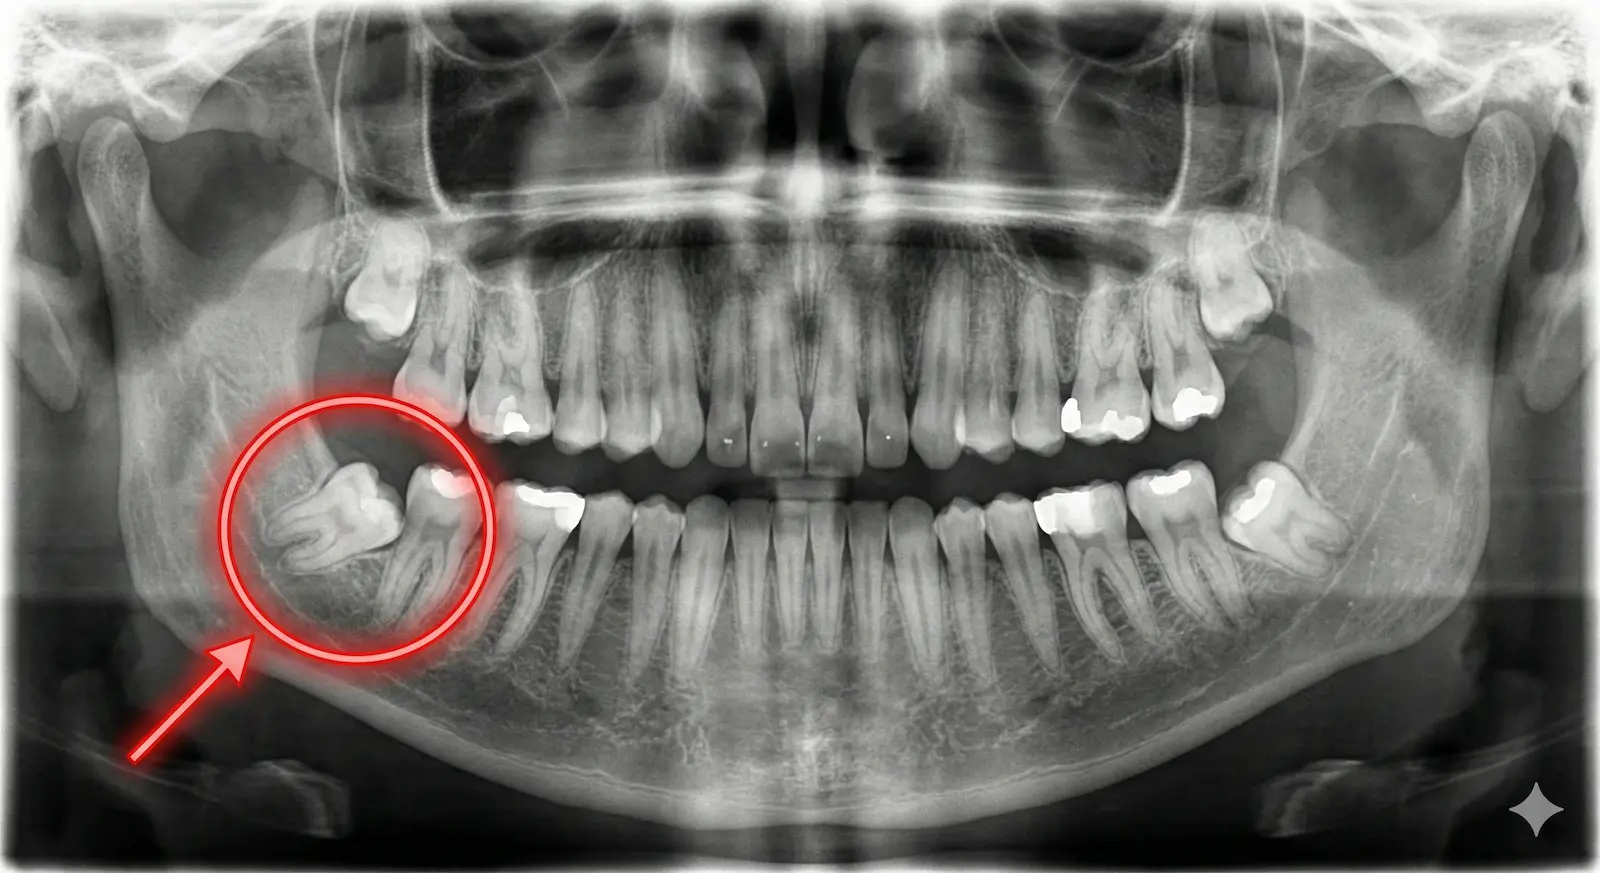

- Tam veya Yarı Gömülü Durumlar: Diş eti altında kalarak enfeksiyona (apseye) yol açıyorsa.

- Öndeki Dişe Zarar Veriyorsa: Yan yatıp öndeki sağlam 2. azı dişine baskı yapıyor ve onu çürütüyorsa.

- Kist Oluşumu: Gömülü dişin çevresinde kist veya tümör oluşumu gözleniyorsa.

Çene ağrılarınız varsa veya 20’lik dişlerinizin durumunu merak ediyorsanız, panoramik röntgen ile kontrol ettirmek için kliniğimize bekliyoruz.